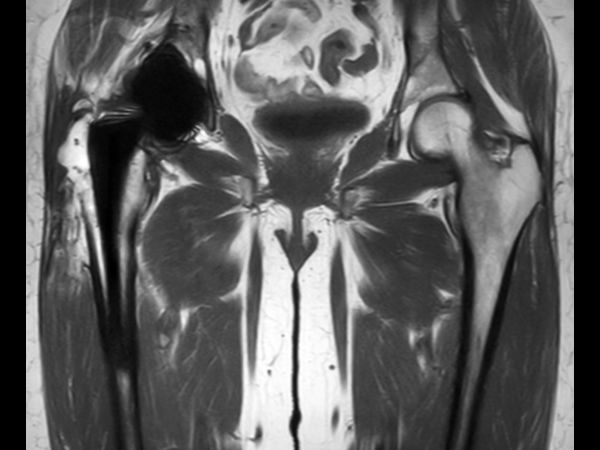

Hip imaging with metal implant

Used Solution

**Only for use with MR Safe or MR Conditional Implants by strictly following the Instructions for Use.